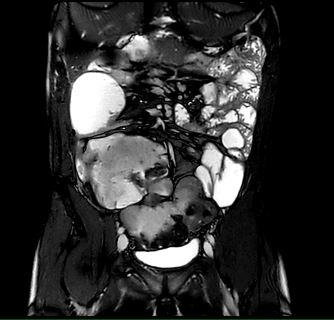

Beispiele von MRT-Dünndarm Aufnahmen

Die Hydro-MRT zeigt detaillierte Bilder des Dünndarms, insbesondere der Darmwand und der umgebenden Strukturen. So können entzündliche Veränderungen, Gewebeschäden, Abszesse, Fisteln und Verengungen frühzeitig erkannt werden.